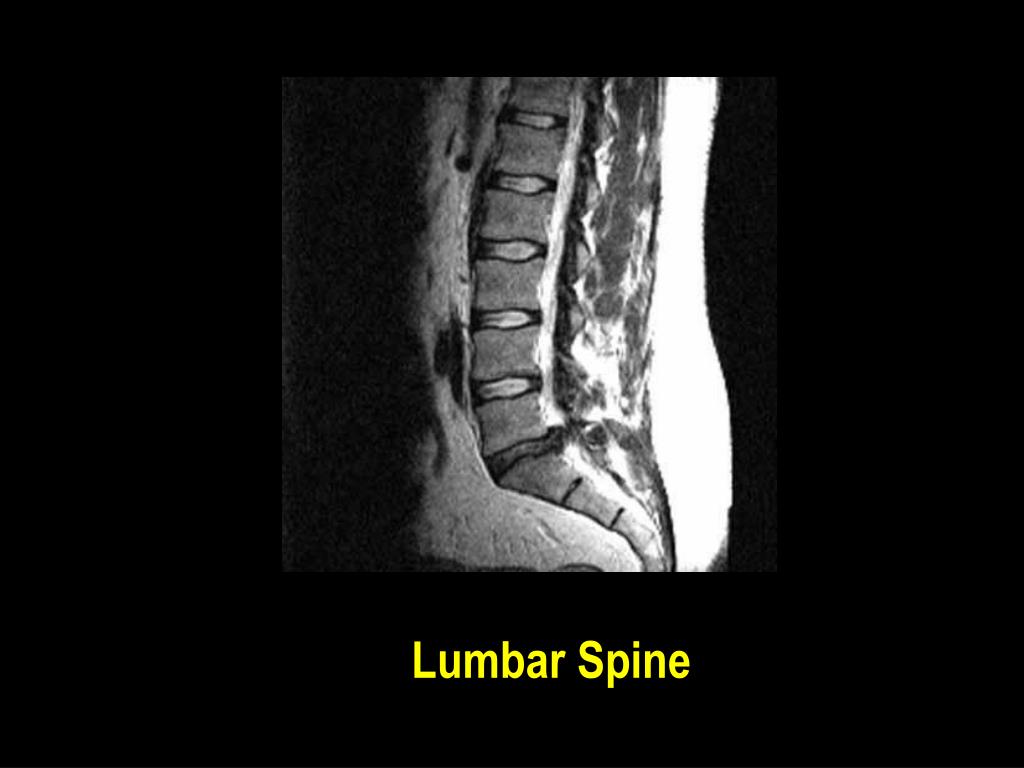

26. Computers used in Diagnosis • Computerised Tomography • Magnetic Resonance Imaging • Ultrasonics • Radioisotope Imaging

34. Lumbar Spine